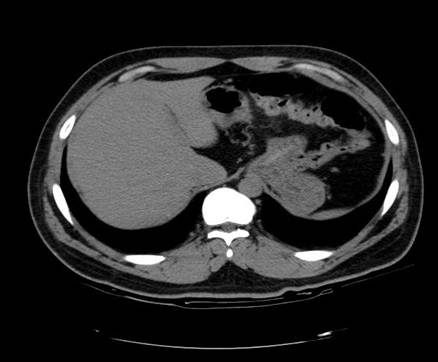

以下是引用zsl6918在2007-6-22 21:08:00的发言:[br]病史较长,反复发作,基本排除恶性病变,腹部定位像可见是小肠梗阻征象,原因无非是肠源性,血管性和神经性的,肠源性的在排除占位后应想到 肠旋转不良的可能,血管性的应想到肠系膜血管的栓塞,神经性的要想到植物神经功能紊乱的可能,本病例应该强化检查帮助诊断,个人感觉旋转不良可能性大。

以下是引用青莲居士在2007-6-24 12:27:00的发言:[br]肠梗阻[br]肝内胆管结石